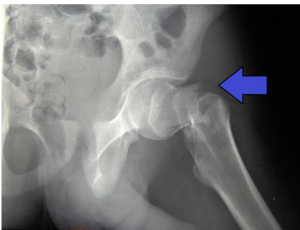

En el último vídeo del canal de ArtroEsport en YouTube, el Doctor Antoni Fraguas te explica una nueva técnica de femoroplastia para reforzar la osteoporosis femoral y evitar su fractura.

En el último episodio de Artro Esport Podcast, el Dr. Fraguas explica las innovaciones que previenen la fractura de fémur. Lo hace en este capítulo en formato entrevista. Asimismo, el

Existe una revolucionaria innovación que previene las fracturas de fémur en ancianos. Los que ya somos mayores hemos escuchado de nuestros abuelos que romperse el fémur a principios del siglo

Los que ya somos mayores hemos escuchado de nuestros abuelos que romperse el fémur a principios del siglo pasado era casi la condena de una muerte escalofriante. Imaginaos: en la